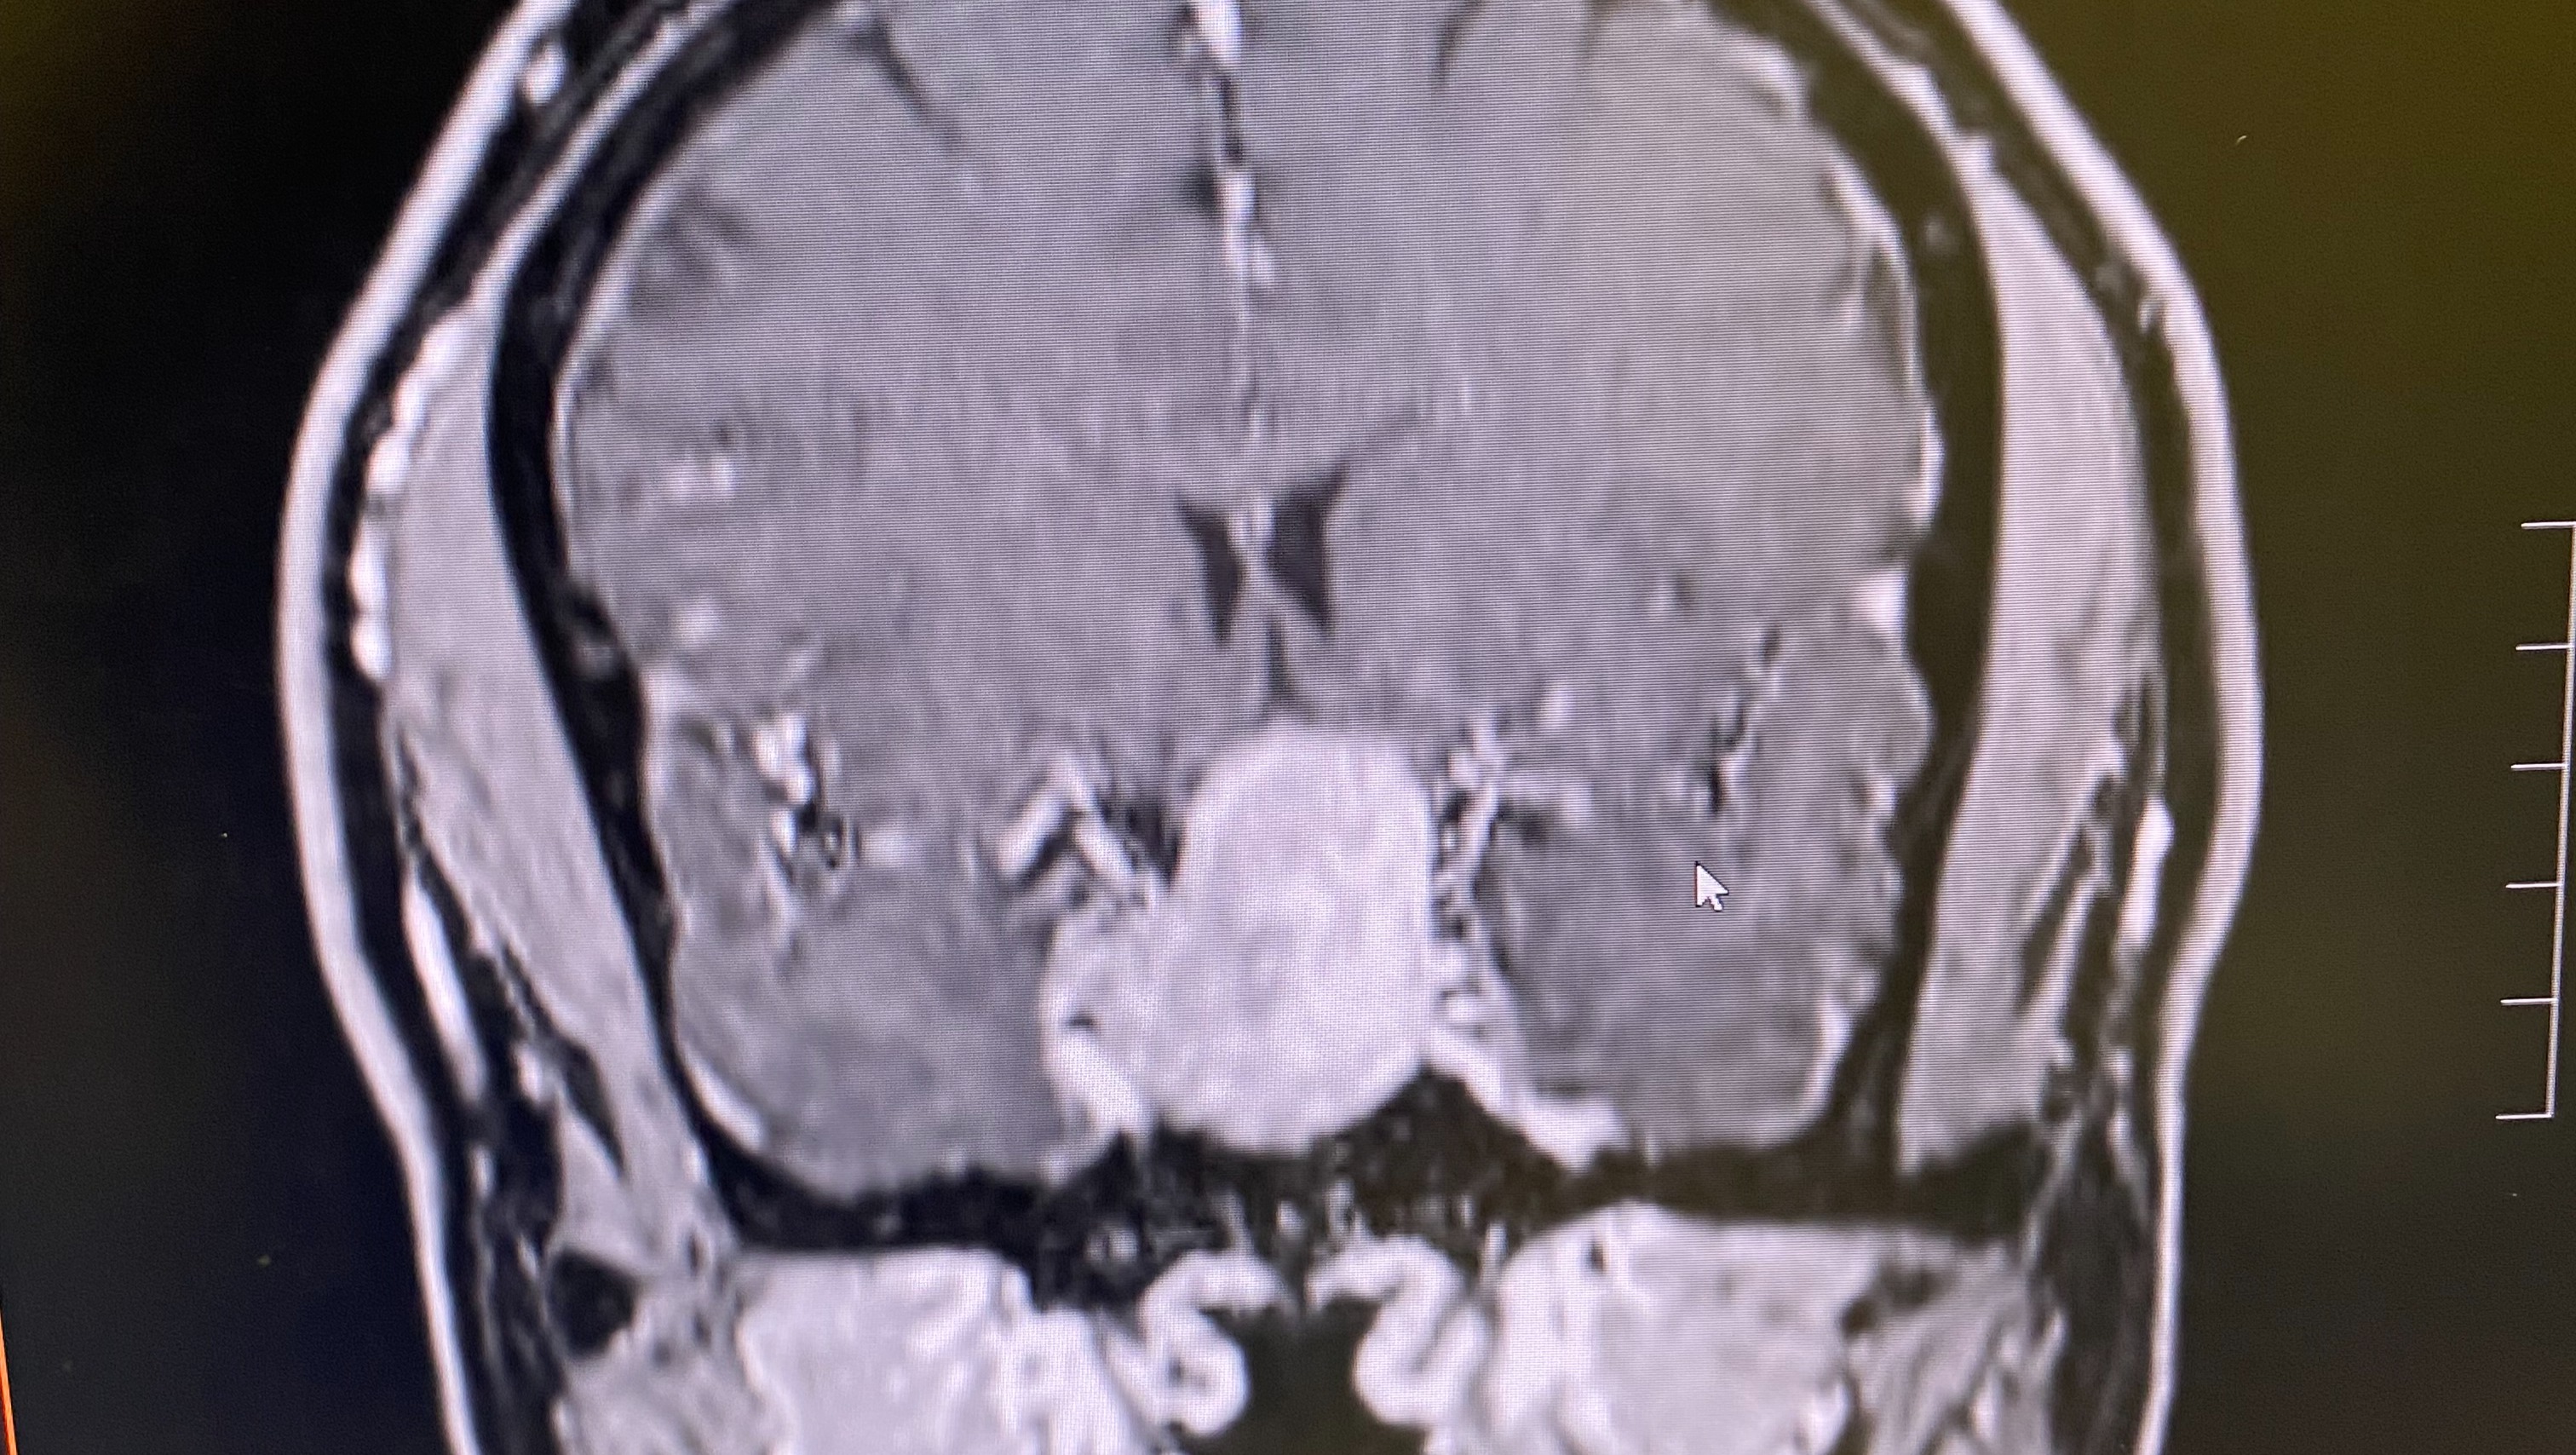

Dear friends, family, and unknown Angels, My name is Shawn Key, and I’m reaching out to share my journey as I battle a brain tumor diagnosed this past December. This fight has not only taken a toll on my physical health but has also led me to make difficult decisions that have changed my life. In November 2025, I made the heart-wrenching choice to shut down my owner operated pest control business. The symptoms I was experiencing became overwhelming. I faced blindness in my left eye, which made it impossible to continue my work, along with dizziness, fatigue, anxiety, and muscle and bone weakness. Simple tasks became monumental challenges, and daily activities that I once took for granted have become daunting. These challenges have not only impacted my ability to work but have also led to significant medical and transportation expenses. That means more than just a major medical procedure—it also means dealing with scans, medications, travel to specialists, and many missed days of work. I will require regular treatments and appointments. Despite these hurdles, I am determined to fight and keep faith in God. However, the financial burden is becoming increasingly difficult to manage. I’m asking for your support to help cover medical expenses, treatments, therapies, medications, transportation to and from appointments, and daily living expenses. With my business closed, I’ve lost a significant source of income. Your support will help cover medical expenses, medication, follow-up tests and treatment expenses, lost income during recovery, rent, utilities, food delivery and groceries, aftercare, travel to post-surgery appointments, and physical therapy. Everyday expenses while recuperating add up quickly. I realize times are hard—no amount is too small, and I certainly welcome your prayers. You’re not just helping me financially—you’re helping me alleviate stress and reminding me that I am not in this fight alone. If you are unable to contribute financially, sharing this campaign with your network would mean the world to me. Your support, whether through donations or sharing my story, is greatly appreciated. Thank you for taking the time to read my story and for considering helping me in this fight. With love and gratitude, Shawn Key